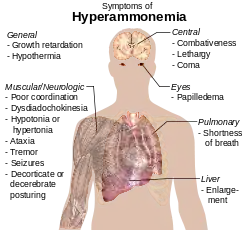

Physiology

Ammonia plays a role in both normal and abnormal animal physiology. It is biosynthesised through normal amino acid metabolism and is toxic in high concentrations. The liver converts ammonia to urea through a series of reactions known as the urea cycle. Liver dysfunction, such as that seen in cirrhosis, may lead to elevated amounts of ammonia in the blood (hyperammonemia). Likewise, defects in the enzymes responsible for the urea cycle, such as ornithine transcarbamylase, lead to hyperammonemia. Hyperammonemia contributes to the confusion and coma of hepatic encephalopathy, as well as the neurologic disease common in people with urea cycle defects and organic acidurias.[164]